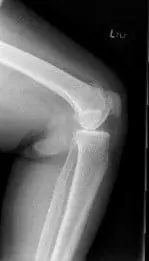

His physical examination revealed tender joint movements with crepitus. There was tenderness on the medial joint line and medial patellar facet. Imaging studies revealed bicompartmental Osteoarthritis of the knee with joint space obliteration of the medial compartment and the patellofemoral compartment.

Pre operative X-Ray of the left knee showing AP and lateral views